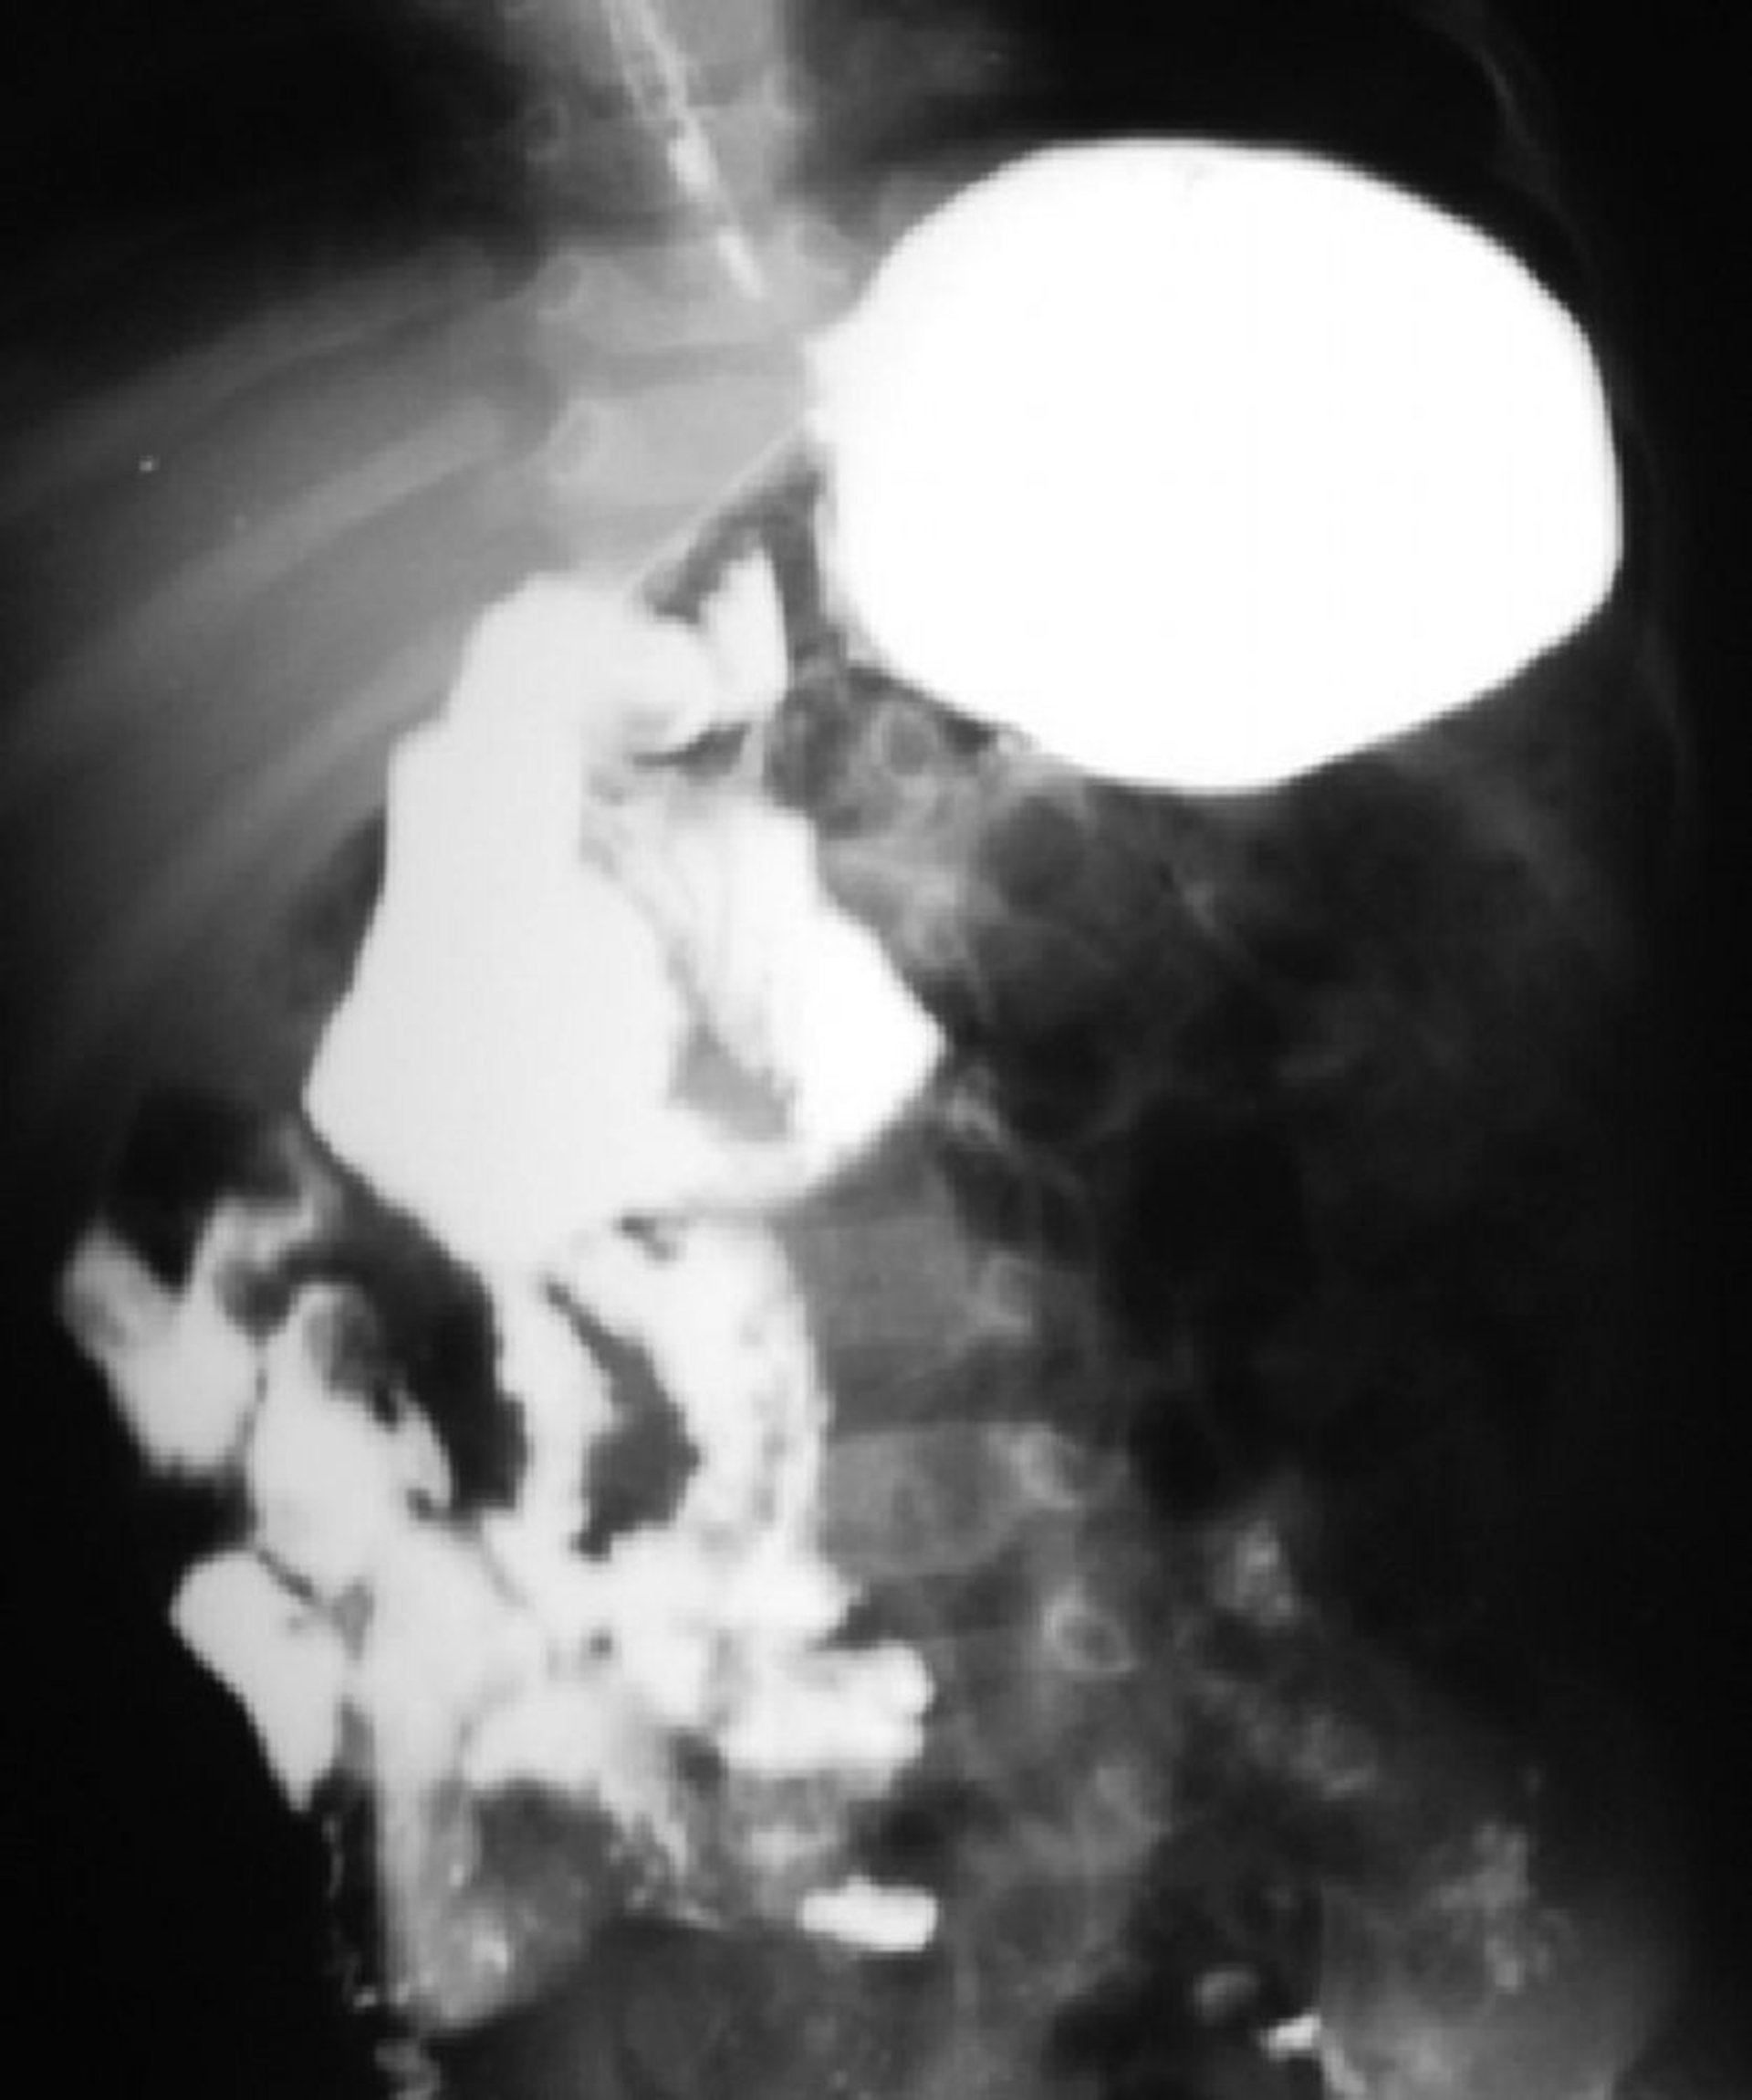

Мальротация кишечника

Это исследование с барием показывает мальротацию кишечника. Дуоденоеюнальный узел находится справа от позвоночника, и большая часть тонкого кишечника находится справа.